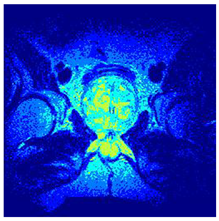

In this subsection, we will discuss the experiment designed to evaluate the performance of EO with cross-entropy for the segmentation of prostate MRI images. To this end, we use a group of reference images formed by a set of six prostate MRI images; see Figure 4. All the images from the group were extracted from the Ferenc Jolesz National Center for Image-Guided Therapy, Harvard Medical School, or Brigham Health Hospital datasets with no additional preprocessing [50]. Prostate MRI images are primarily used for disease diagnosis or to establish treatment for prostate-related diseases such as prostatitis, benign prostatic hyperplasia (BPH), and prostate cancer, among other diseases or medical conditions. In the context of this article, the images were used to test the efficiency of the equilibrium optimizing algorithm and compare it with the other six chosen algorithms. The segmentation of MRIs is carried out over four different thresholds levels: = 3, 4, 5, and 8. Due to the nature of the images, there was a limited number of different tissues in the images; thus, there was no point in evaluating a larger number of .

Figure 4.

Eleven transaxial-cut prostate MRI images. This figure presents a set of eleven transaxial-cut magnetic resonance (MR) images of the prostate. These images serve as the input dataset for evaluating the segmentation performance of the proposed algorithm.

Table 5 presents the segmentation of the MRIs using EO for a qualitative inspection. From Figure 5, it is clear that two lumps in the prostate have been highlighted by the thresholding process. Prostatic MRIs present noisy conditions, which makes it difficult to visualize the thresholding with the naked eye, so in Figure 5 we present the thresholded image as well as the histogram with the values of the thresholds generated by the EO. It can be observed in the histogram that the thresholds present an adequate distribution, even though this particular image has impulsive noise and a simple shape. Our findings indicate that four thresholds are typically sufficient for this application, which corresponds to identifying five different tissue types in the image. A smaller threshold value may result in a lack of sufficient contrast to highlight relevant anatomical structures, such as the prostate capsule. In contrast, a higher number of thresholds may lead to the incorrect differentiation of anatomical regions that should be connected.

Table 5.

Segmentation of transaxial-cut prostate MRI images Using EO and cross-entropy. This table presents the segmentation results of transaxial-cut prostate MRI images using the equilibrium optimizer (EO) and cross-entropy. Each row corresponds to a distinct MRI image, while the columns nt represent the number of thresholds applied during segmentation. The results illustrate the performance of the EO algorithm across different threshold levels for each image.